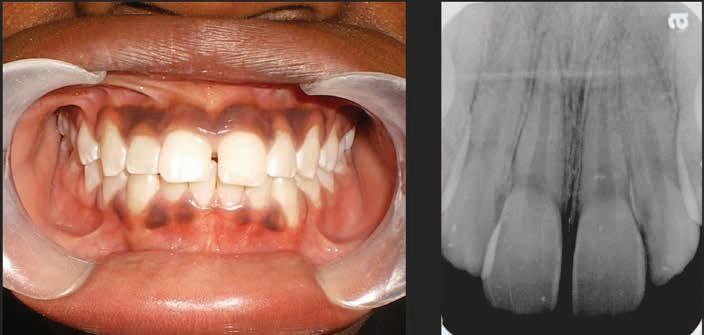

An otherwise healthy African American male, age 58 years old, presented to the UTHealth Houston School of Dentistry with a chief complaint of a facial rash. (right and below).

The patient’s vital signs were: Blood Pressure: 142/92; Pulse: 72/minute; Respiration: 14/minute; Patient’s height: 5’10”; and Weight: 175 pounds. The patient stated that he was not taking medications for systemic diseases, had no allergies, and had not received a current shingles, pneumonia, or influenza vaccine. The patient also stated that he visits his dentist, “once every year or so,” which indicates a slightly less than recommended twice a year clinical exam, but also suggests the patient seeks semi-routine dental examination.

Upon clinical examination the patient exhibited good oral hygiene and had no visible caries. The patient’s existing dental findings included several crowns and amalgam restorations.

Intraoral examination showed multiple ulcerative type lesions located on the non-keratinized tissue of the inner mandibular lip. The lesions

simultaneously presented with a leukoplakic covering over an ulcerated base. Given the patient’s outer facial appearance of the rash with many of the lesions crusted over, it can be postulated that the intraoral lesions were previously blistering and at clinical examination were beginning to heal. The patient did not complain of dental pain. No radiographs were obtained due to the nature of the chief complaint of a facial vesicular rash.

Further, the patient did not exhibit the trio of symptoms of Ramsay Hunt Syndrome; one-sided facial paralysis, otalgia, and a vesicular rash and was removed as a possible diagnosis. Because there was no facial paralysis, a Bell’s palsy diagnosis was also eliminated. Additionally, herpes simplex virus was not considered in the differential diagnosis due to the presentation of lesions on the nonkeratinized mucous membranes of the inner lip. Herpes simplex virus most often is seen on the keratinized gingival mucosa and are commonly referred to as oral cold sores that are often reported as recurrent in the patient medical history. Given the patient had not been vaccinated against shingles and the clinical presentation of the rash, differential diagnosis was determined to be herpes zoster.